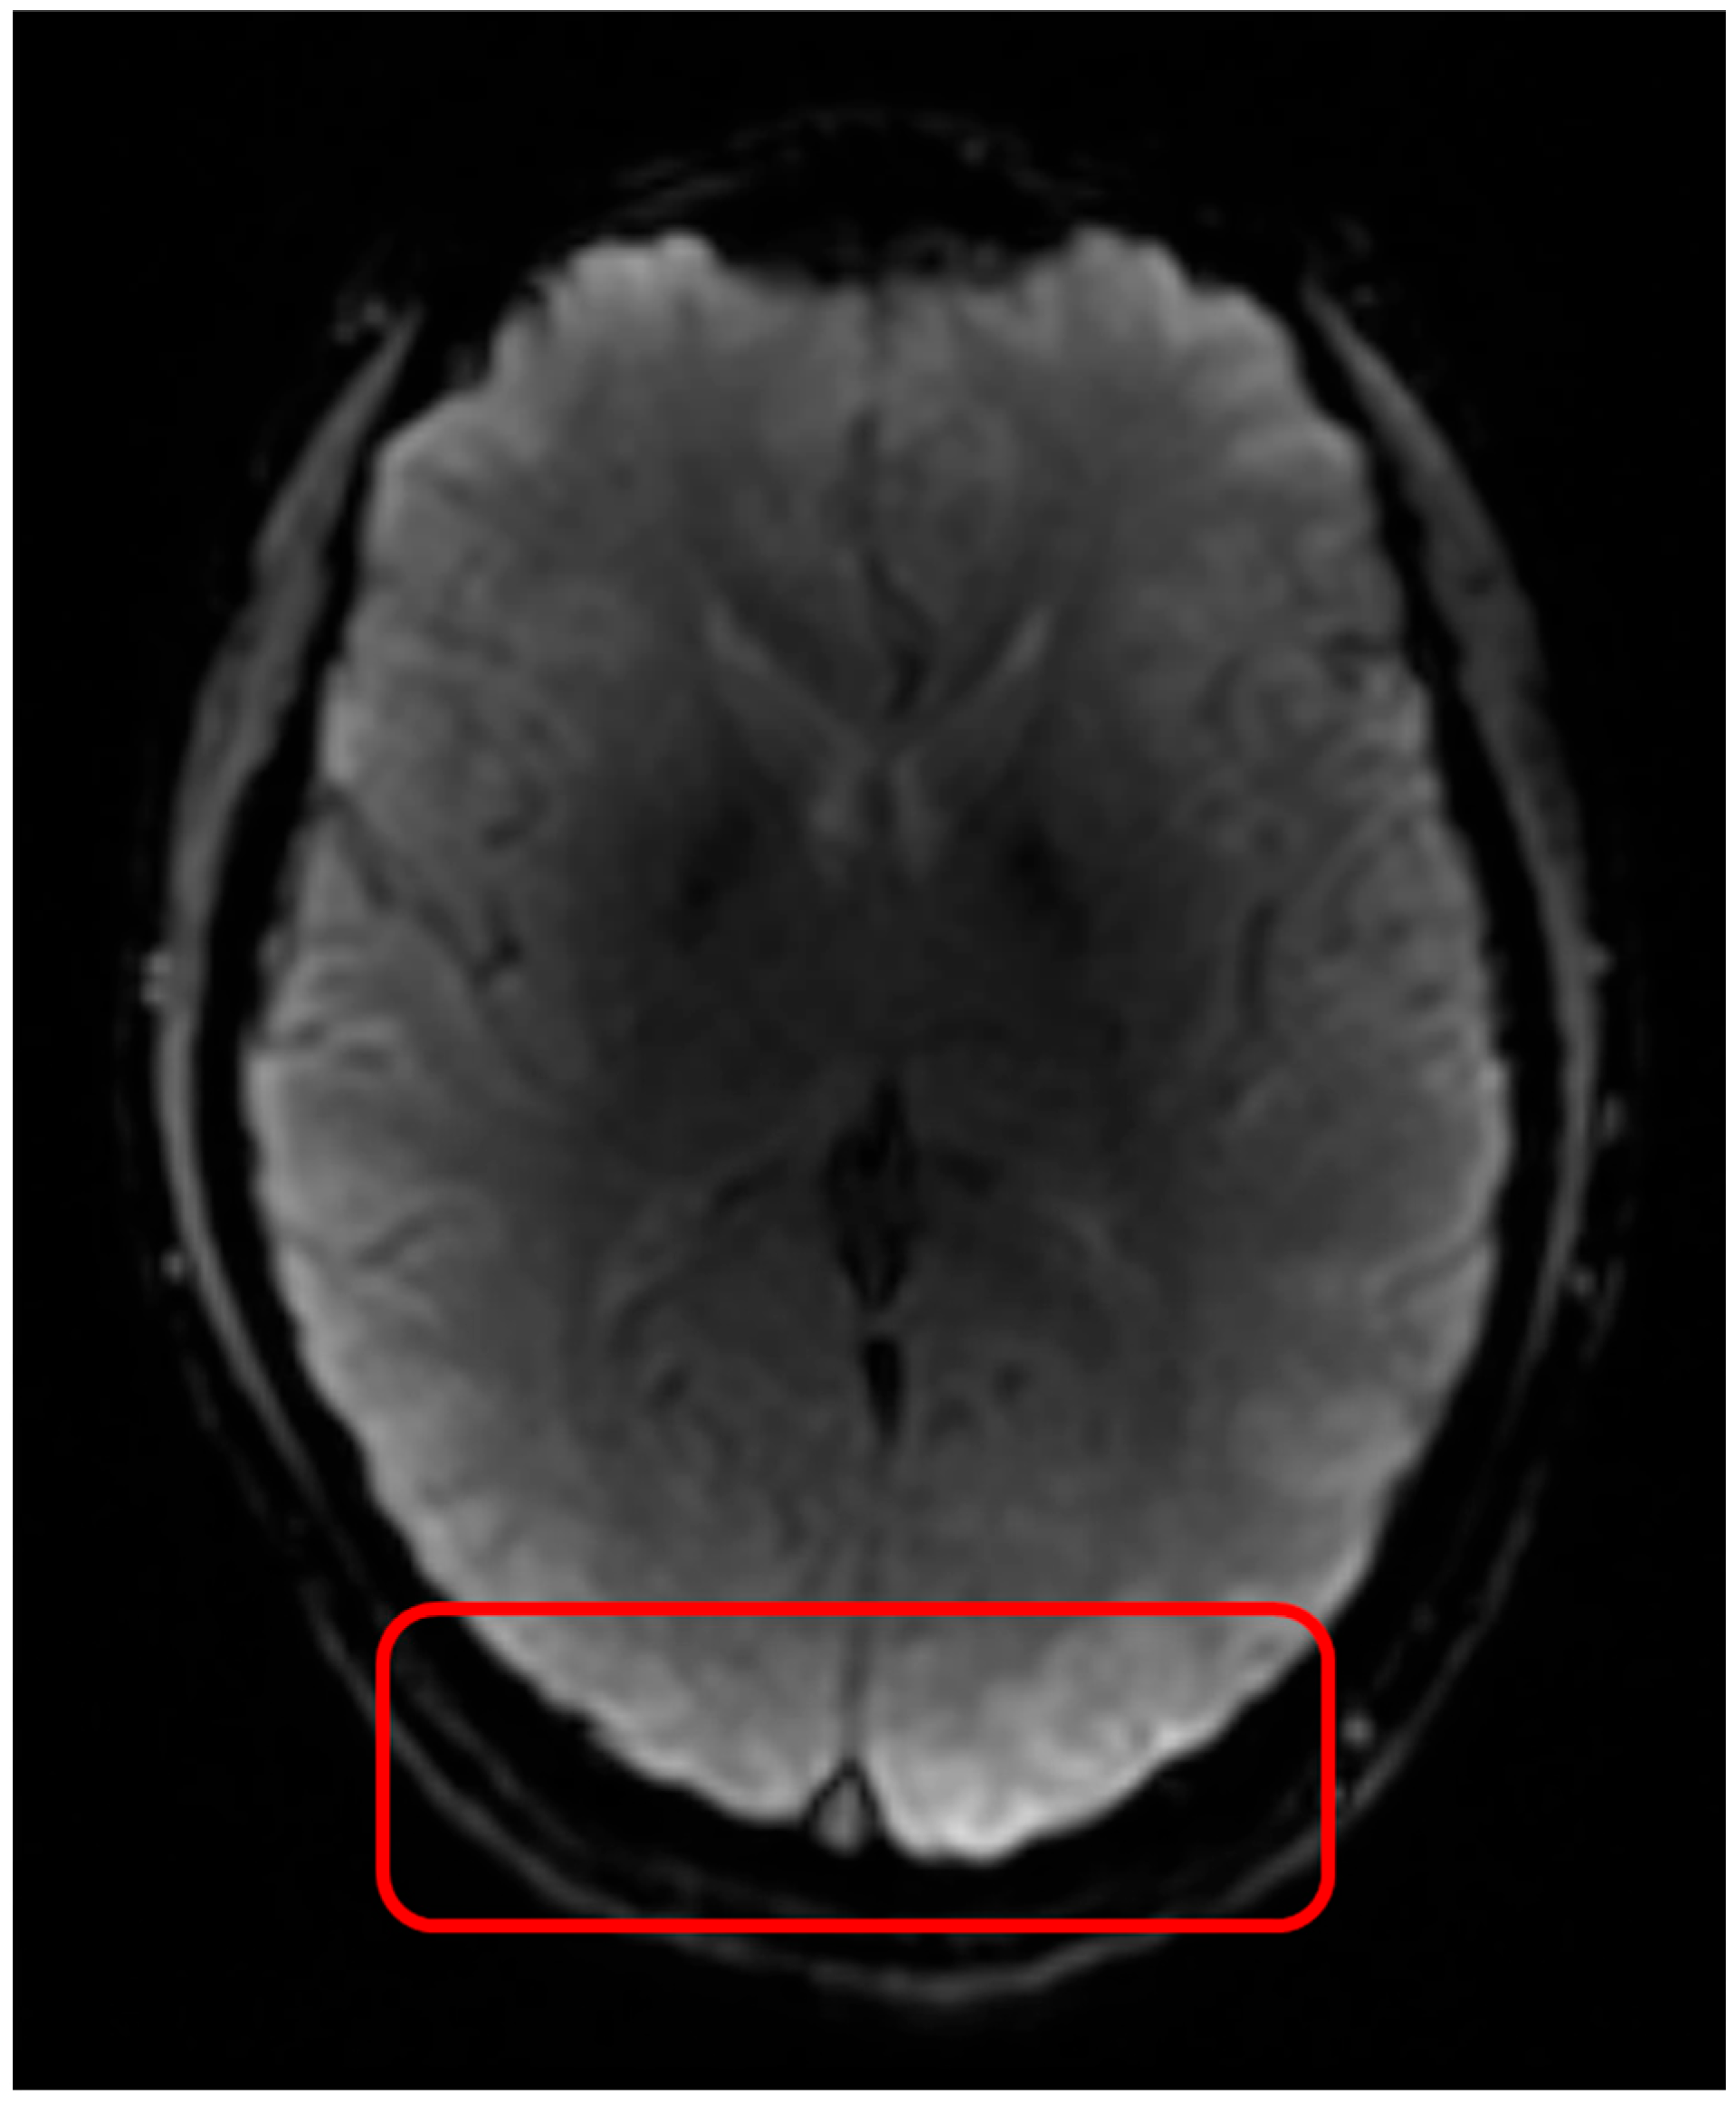

Figure 2. Geometric distortions in DSC MRI appear as misshapen or incorrectly sized brain structures, leading to spatial misregistration with anatomical images, primarily in regions near air/tissue interfaces. Geometric distortions in DSC MRI arise due to B0 field inhomogeneities and tissue susceptibility differences. On the left is a T1w MRI scan and on the right a DSC MRI scan with visible geometric distortions. The red square indicates tissue hyper intensities due to B1 field inhomogeneities.

Geometric distortions in DSC MRI result in misshapen or incorrectly sized brain structures, leading to spatial misregistration, causing the observed anatomical locations to deviate from their true anatomical positions (Figure 2). This can result in anatomic alterations observed in DSC MRI that do not correspond with the actual location of pathological tissue. Geometric distortions in EPI sequences commonly arise close to regions where the magnetic tissue properties change abruptly (like air, bone, and brain tissue), which impact the static B0 field [19,20,21,22,23]. This type of geometric distortion typically appears as deformations in the phase-encoding direction, most prominent near air–tissue interfaces such as the sinus areas in the brain. Geometric distortions can make certain areas in the brain appear in incorrect locations, have distorted shapes, or as ‘signal pile-up’ where signal from multiple voxels are displaced into a single voxel, causing localized signal increase, which complicates accurate brain mapping, diagnosis, or surgical planning.